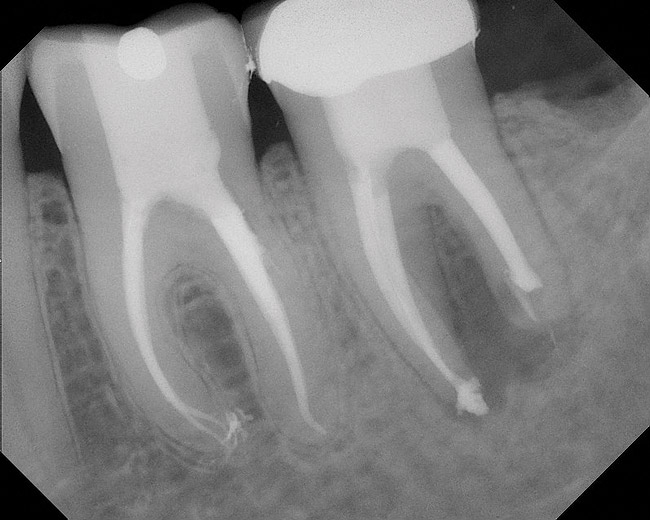

Figure 9  Clinical case of invasive cervical resorption that was deemed nonrestorable and the tooth removed.

Figure 9

Figure 10  Clinical case of idiopathic resorption of the upper second bicuspid. The tooth was deemed hopeless and extracted.

Figure 10